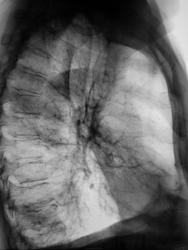

Очень похоже на ателектаз средней доли. Крупные кольцевидные тени. Может быть буллёзные изменения.

А почему не пневмоторакс?

Потому,что лёгочный рисунок везде есть.

Прямая проекция. Там, где должна быть нижняя доля. Где легочный рисунок?

Прямая проекция. Там, где должна быть нижняя доля. Где легочный рисунок?=

Он есть, просто "перебит". Нет, не пневмоторакс, что Вы? Если эту грубую тяжистость принять за край лёгкого, то "он" идет выше, там лёг. рисунок уже чётко виден. И где на боковом? При таком поджатии, хоть по передней,хоть по задней поверхности немножко воздуха бы было.

Согласен с ателектазом средней доли и вздутием (эмфиземой) соседних сегментов, дающих резкое повышение прозрачности и "поджимающих" среднюю долю туда, где мы её видим.

Есть такое понятие "среднедолевой синдром" Думаю, из этой серии. Среднедолевой бронх тонкий и короткий, легко сдавливается (чем угодно)

Может, просто фиброз (дай-то Бог), может, бронхоэктазы? А может, и рак, и сдавление лимфоузлами.

Не пневмоторакс это точно. Ателектаз средней доли. Синдром средней доли подходящее заключение.

Заключение Вам тут, в основном, уже "состряпали": Среднедолевой синдром: ателектаз? Фиброз? Дифференцировать фиброз, ателектаз. Настороженность по CA. Я бы так написал:)

имеется ателектаз и инфильтрация справа. В нижней доле справа мелкие очаги(на томограммах). Пролечить как пневмонию, потом сделать контроль.

Такая мощнейшая шварта, по всей видимости. возникла в результате перенесенного плеврита?